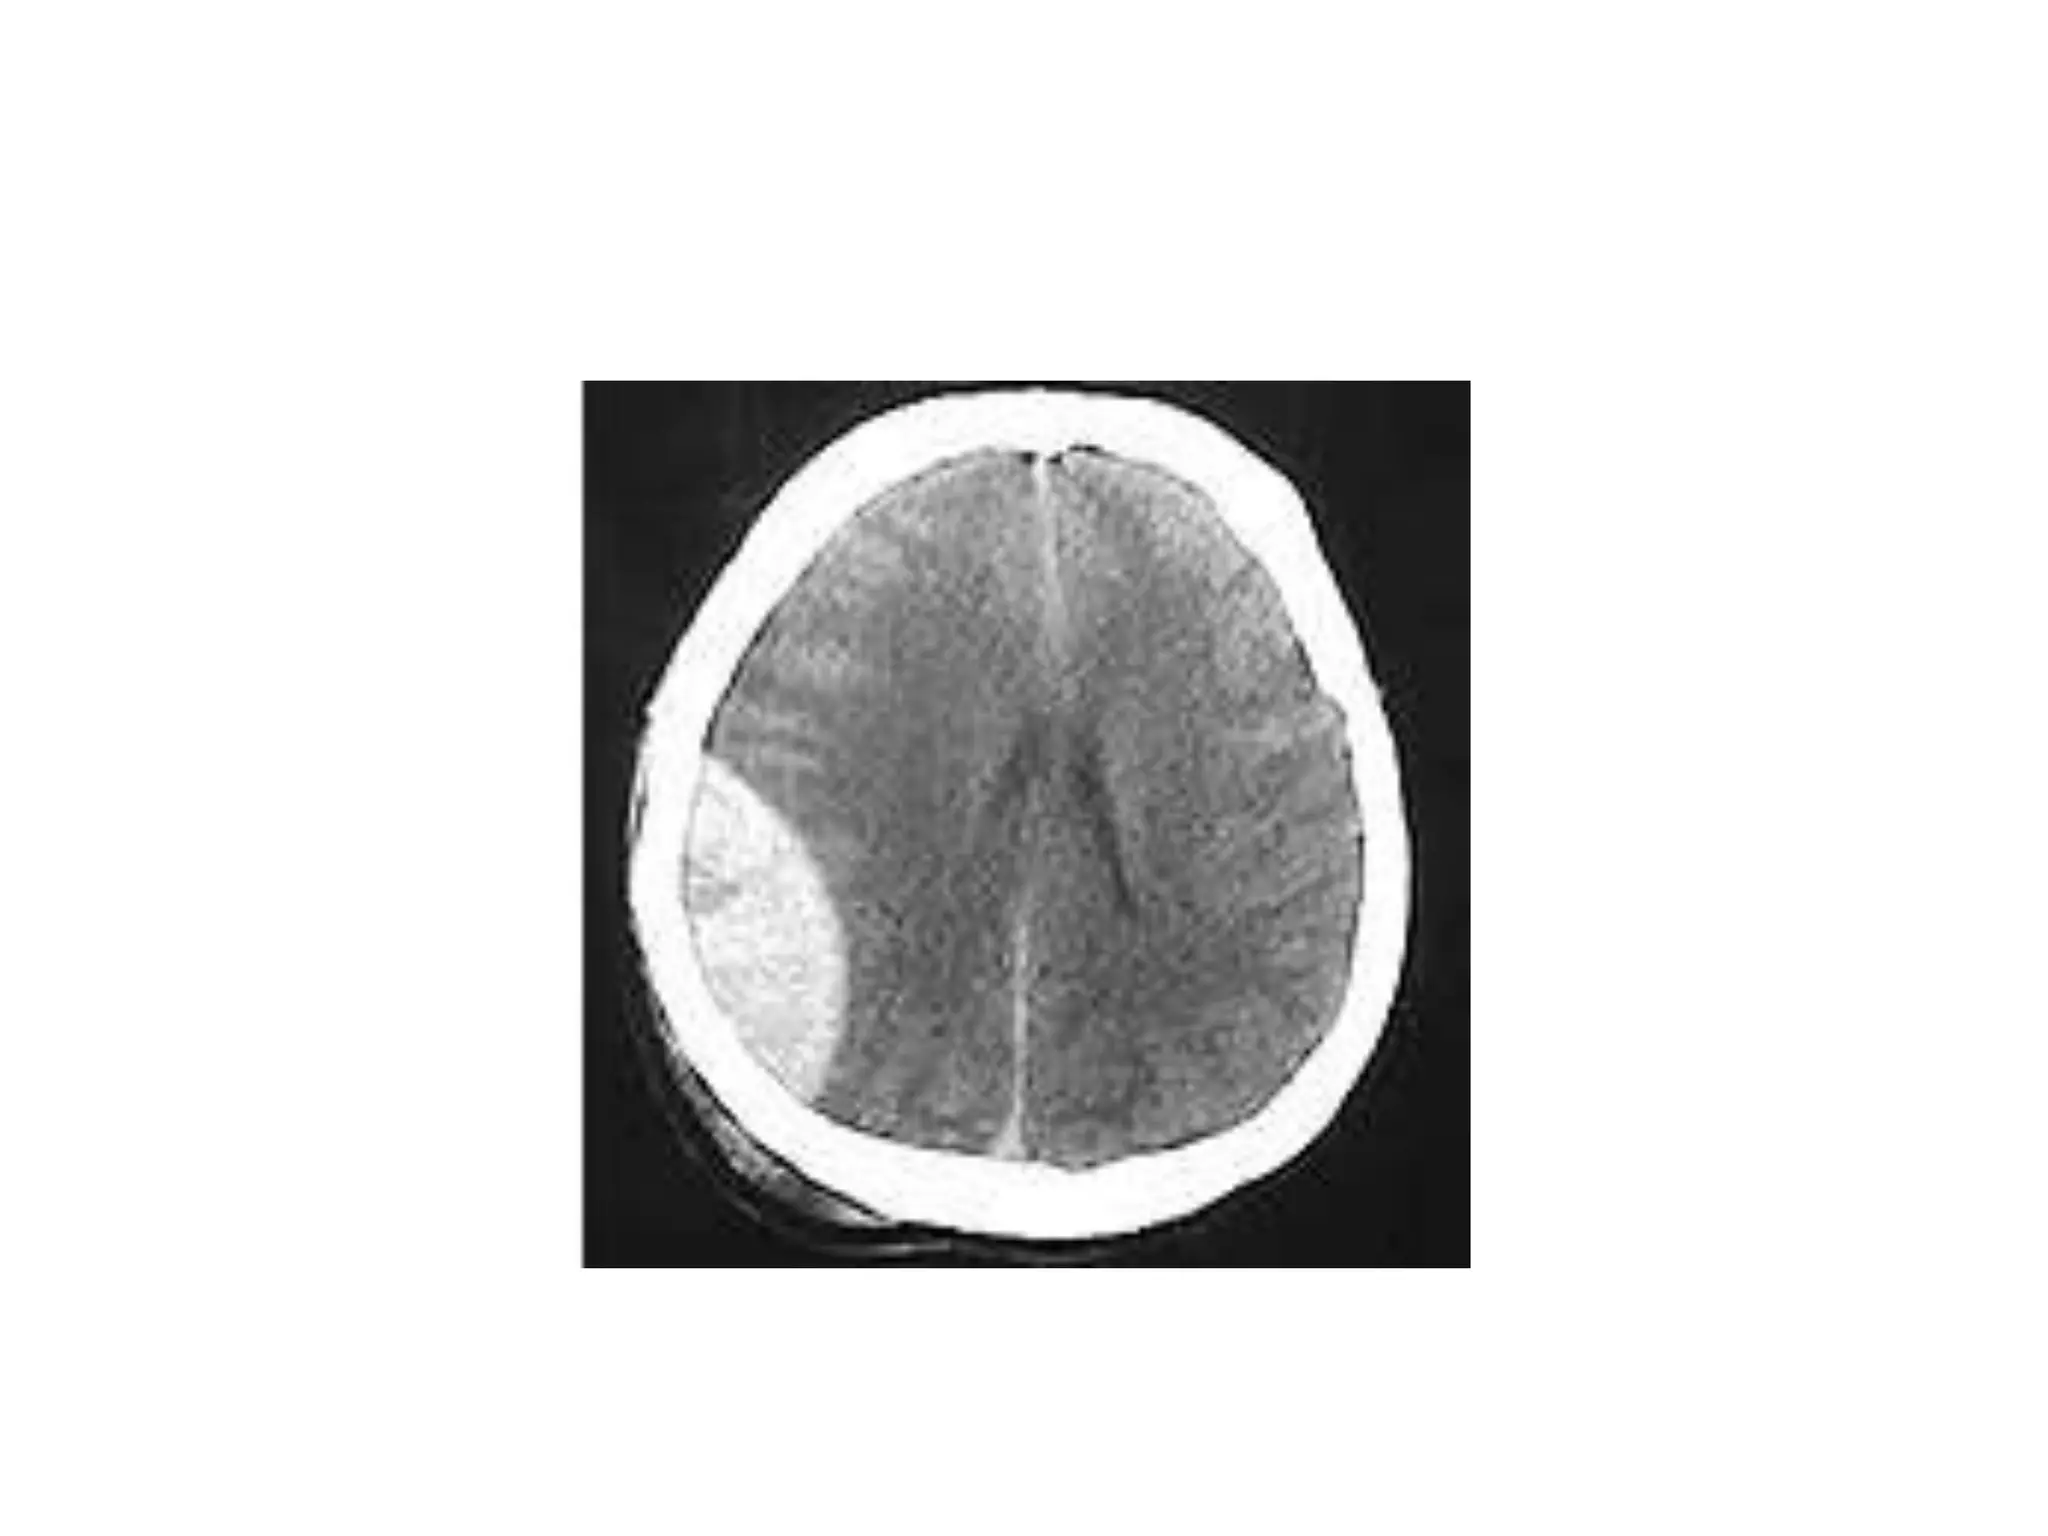

This document provides an overview of key topics in chest x-rays, ECG readings, medical instruments, drugs, and clinical pictures commonly seen in medical orientation classes. It lists various chest x-ray findings like pleural effusion, pneumonia, and pulmonary edema. It also outlines different ECG waves and conditions such as atrial fibrillation, heart blocks, and left ventricular hypertrophy. Common medical instruments like oropharyngeal airways, IV cannulas, and Foley catheters are identified. Examples of anti-tuberculosis therapy, steroids, and clinical pictures including butterfly rash and Cushing's face are briefly covered.